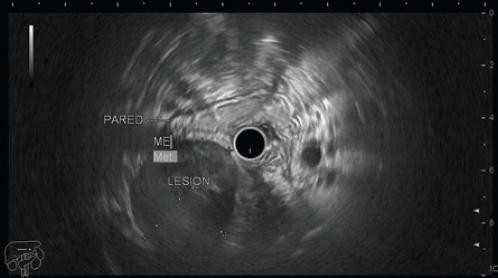

Mujer de 53 años con antecedente de hipertrigliceridemia en tratamiento con fibratos. Es referida por historia de 3 años de evolución de pérdida de peso y saciedad temprana, progresivamente se agrega plenitud posprandial y masa palpable en el epigastrio, motivo por el que se realiza una tomografía contrastada toracoabdominal que reporta una lesión homogénea de contorno bien delimitado en la pared del cuerpo gástrico, de 7.5 × 5.7 × 5.8 cm (Fig. 1). Se realiza endoscopia superior y se encuentra una lesión subepitelial umbilicada en la curvatura menor a nivel de la unión del cuerpo con el antro gástrico (Fig. 2); se complementa con sonografía endoscópica (Fig. 3), con hallazgo de una lesión sólida hipoecoica en la pared gástrica que se origina en la capa muscular externa, bien circunscrita, con medidas de 4.9 × 4.3 cm. Se toman biopsias por aspiración con aguja fina, con reporte de citología transprocedimiento de tumor fusocelular. Se decide el manejo quirúrgico por sospecha de tumor del estroma gastrointestinal (GIST, gastrointestinal stromal tumor) y por la sintomatología en ese momento (Fig. 4). Durante la intervención se encuentra una tumoración firme en la curvatura menor que se extiende al antro gástrico. Se realizan gastrectomía distal (Fig. 5) y anastomosis gastroyeyunal en Y de Roux, sin complicaciones durante el procedimiento.

Figura 3 Sonografía endoscópica que muestra una lesión en el cuerpo gástrico, hipoecoica y de bordes definidos.